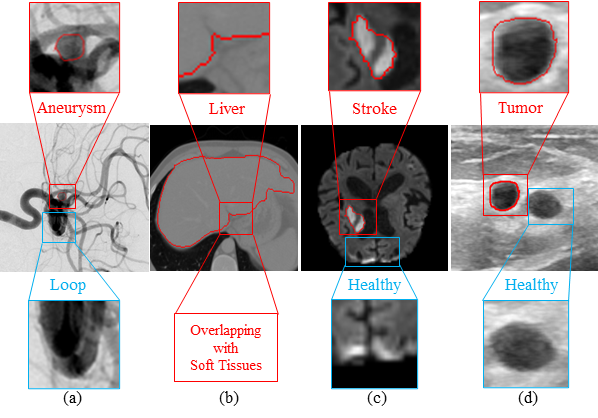

Accurate delineation of regions of interest (ROI) from surrounding vasculature or tissues is fundamental for developing reliable clinical management strategies[8272030]. However, constructing a unified medical image segmentation framework that can robustly generalize across both vascular and non-vascular pathological and non-pathological structures, while maintaining consistent performance across diverse imaging modalities, remains a major challenge. Even within the cardio and cerebrovascular domains, segmentation tasks exhibit domain-specific and modality-dependent complexities. For instance, cerebral aneurysm segmentation in Digital Subtraction Angiography (DSA) must contend with extremely small, irregular lesions embedded within dense, overlapping arterial networks, where aneurysmal sacs often share identical dye intensities with surrounding vessels. Conversely, ischemic stroke segmentation in MRI is hindered by diffuse and temporally evolving lesion boundaries. Extending segmentation to non-vascular diseases/organs or alternative imaging modalities further amplifies these challenges. For example, Computed Tomography Angiography (CTA) based liver segmentation suffers from heterogeneous contrast phases and adjacent organ interference, while breast tumor segmentation in ultrasound is degraded by speckle noise and operator-dependent variability. Fig. 1 emphasises both disease as well as modality-specific challenges in medical image segmentation. When optimized solely using region-centric objectives, even strong backbones such as UNet [ronneberger2015u], UNet++ [10.1007/978-3-030-00889-5_1], SwinUNetR [hatamizadeh2021swin], and TransUNet [CHEN2024103280] often produce discontinuous contours, particularly in small or low-contrast structures.

Refer to caption

Fig. 1: Challenges in medical image segmentation across different modalities: (a) DSA: a partially hidden aneurysm behind the cluttered arteries and loops having similar dye contrasts, (b) CTA: an overlapping soft tissues with liver due to low tissue contrast, (c) MRI: an irregular boundaries and identical contrast of stroke and healthy tissue, and (d) Ultrasound: similar tumor and healthy tissue structure in breast.